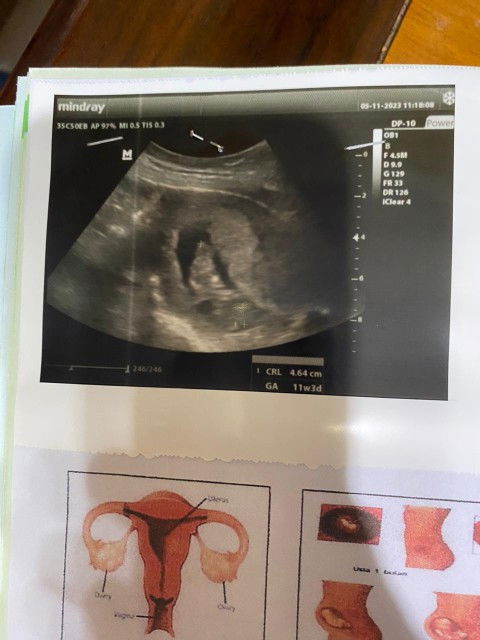

Halo bunda2, salam kenal. Tadi aku abis usg di usia kehamilan 11w3d. Alhamdulillah kata dokter semua aman, normal, dan janin aktif krn banyak gerak. Djj juga aman walaupun aku ga tau berapa djjnya. Aku ga banyak tanya dan ga banyak dijelasin krn dokter buru2 dan antre.. ga tau kenapa masih ada kekhwatiran di aku apalagi ga ada cek NT:( Aku udh cek google beberapa istilah usg, tapi aku ga tau arti dari keterangan di samping kanan itu (F, D, G, FR, dll.) Apa bunda2 di sini ada yg lebih paham sama hasil usg aku? Kalo ada boleh sharing yaa bun. Terima kasih.. #bantusharing #ingintahu #firstmom